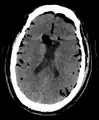

CT scans of patients with a tension pneumocephalus typically show air that compresses the frontal lobes of the brain, which results in a tented appearance of the brain in the skull known as the Mount Fuji sign.[1][2][3] The name is derived from the resemblance of the brain to Mount Fuji in Japan, a volcano known for its symmetrical cone. In typical cases, there is a symmetrical depression near the midline (such as the crater of a volcano), due to intact bridging veins.[3] Its occurrence seems to be limited to tension pneumocephalus (not occurring in pneumocephalus without tension).[4] The sign was first described by a team of Japanese neurosurgeons.[5]

Large pneumocephaly secondary to surgical wound